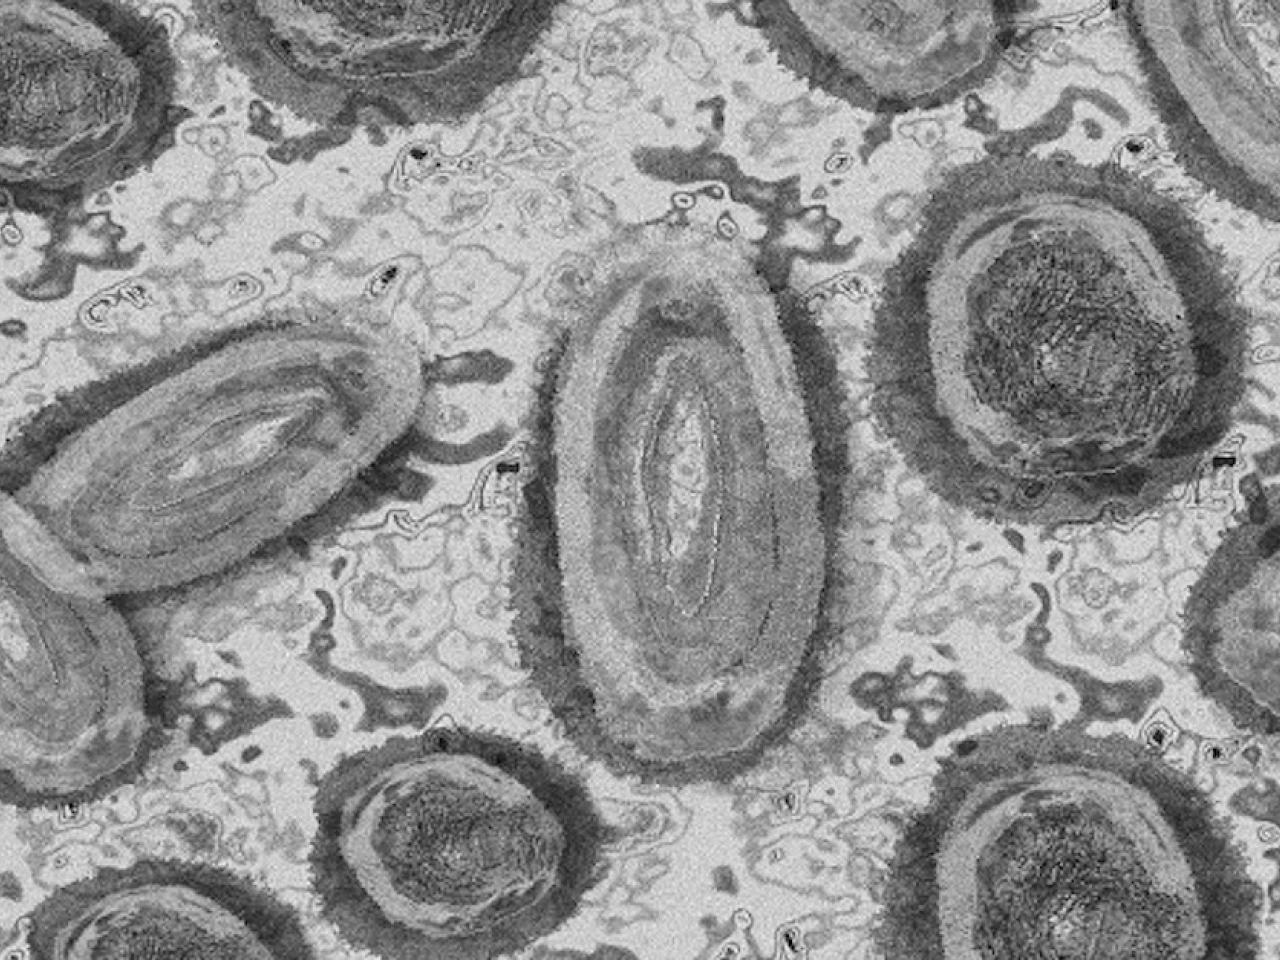

Ministerio de Salud confirma primer caso en Ecuador de la Viruela del Mono

Ecuavisa

El Ministerio de Salud Pública (MSP) confirmó este miércoles 6 de julio el primer caso de viruela del mono en Ecuador.

"Se trata de un paciente de 30 años que presentó síntomas relacionados con la enfermedad: fiebre, decaimiento, malestar general y vesículas (similares a los granos)", indicó el MSP en un comunicado.